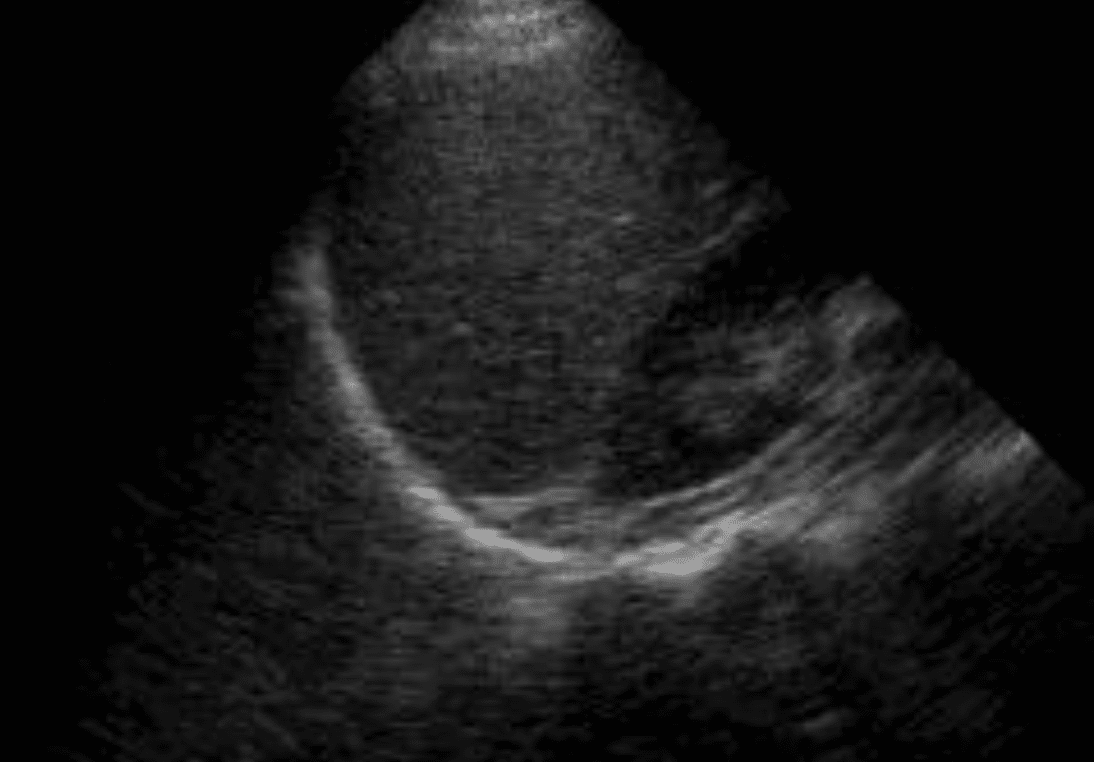

8. Subxiphoid view (or Parasternal Long Axis)

- Labelled SUBX (or PLAX)

- Transverse view

- Demonstration of the pericardium